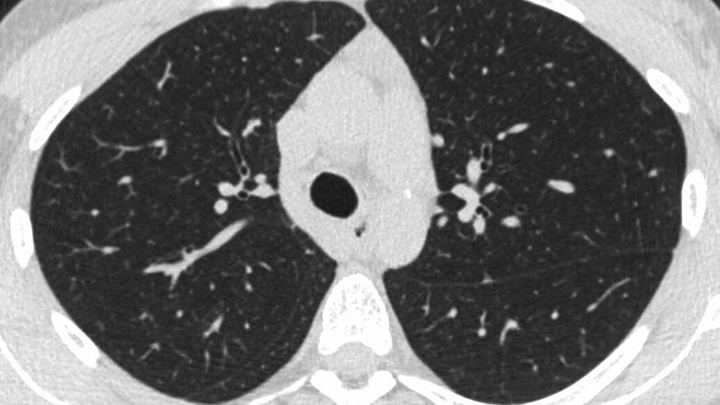

Диагностика EVALI: как выявляют

Чтобы установить диагноз, специалист собирает анамнез: уточняет, как давно развились симптомы, пользуется ли пациент вейпами, и если да, то какими жидкостями. Также проводится аускультация легких (прослушивание), — чтобы выявить хрипы и оценить частоту дыхания.

Также проводится рентгенография грудной клетки. Рентген часто показывает двусторонние инфильтраты (затуманенные участки) — признаки воспаления в легких. Если же исследование недостаточно информативно (а так бывает часто из-за низкой чувствительности теста), также выполняют компьютерную томографию (КТ), которая показывает очаги воспаления и участки утолщения интерстициальной (соединительной) ткани.